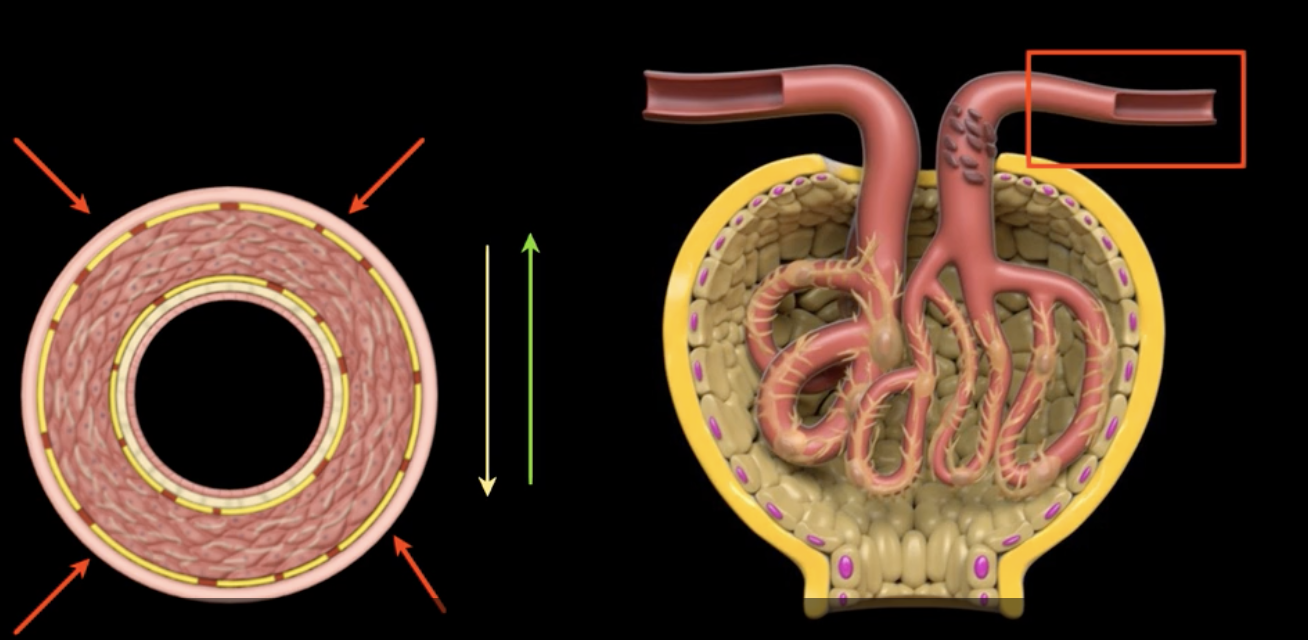

which decreases HPg and GFR, and causes decreased urine volume

Vasoconstriction of the afferent arteriole decreases blood flow into the glomerulus…..

which also decreased HPg and GFR, causing decreased urine volume

Vasodilation of the efferent arteriole increases flow out of the glomerulus…

macula densa cells stimulate afferent arteriole vasoconstriction to reduce GFR, slowing filtrate flow and optimizing reabsorption

high concentrations of Na+ and Cl- in the filtrate indicate high flow rate with decreased reabsorption. causing?